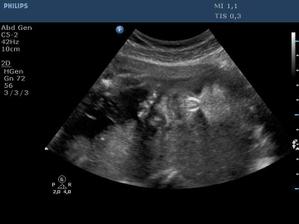

Ultrazvuk miminka - 24 týden

Z "menší protekce" u pana primáře Radiodiagnostického oddělení jsme mohli na soukromou "špionáž" naší krásné holčičky... (Pan doktor je už třetí, kdo hádá holčičku a po pravdě s tím přístrojem, co má k dispozici, bylo naprosto zřetelně vidět, že tam žádný pytlík není! :o)) Natočil nám i několik videí, kde ta naše šibalka zívala a dvakrát na nás dokonce vyplazovala jazyk. ;o)